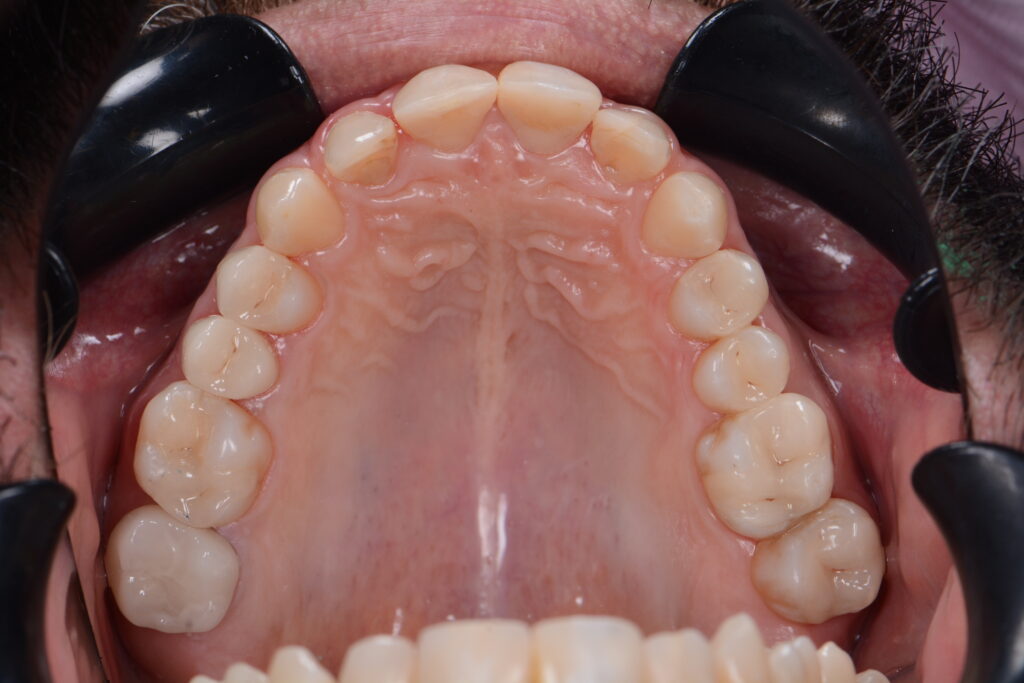

Kunststofffüllungen – oft auch als Kompositfüllungen bezeichnet – sind langlebige weiße bzw. farblich den Zähnen gleichende Füllungen. Sie können selbstverständlich auch verwendet werden, um Backenzähne zu reparieren. Bei Backenzähnen mit Karies, Rissen, Brüchen oder anderen Defekten wird dann der defekte Teil des Zahns entfernt, und der entstandene Hohlraum wird mit einer Kompositfüllung zum ästhetischen Ersatz der Zahnsubstanz befüllt.

Früher wurden im Seitenzahnbereich sehr häufig Amalgamfüllungen verwendet. Diese metallfarbenen Zahnfüllungen sehen nicht nur wenig ästhetisch aus, sie setzen auch Quecksilber frei und sind damit eine potentielle Gesundheitsgefahr. Wenn Sie Ihre alten Amalgamfüllungen entfernen lassen möchten, kommen Kunststofffüllungen als weitgehend unbedenklicher Ersatz infrage.

Möchten Sie noch mehr Fotos Fotos von Kompositfüllungen sehen? Folgen Sie Dr. Azzawi auf Instagram: